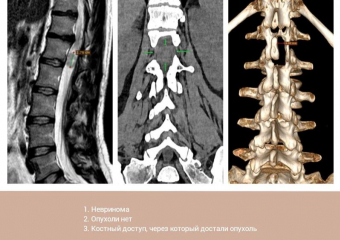

Опухоль из позвоночника через крошечный разрез удалили пациентке нейрохирурги Пятигорска

Почти год мучилась 28-летняя жительница Ставрополья от боли. Сначала у нее ныло в тазобедренном суставе, потом нога начала неметь, а затем появились проблемы...